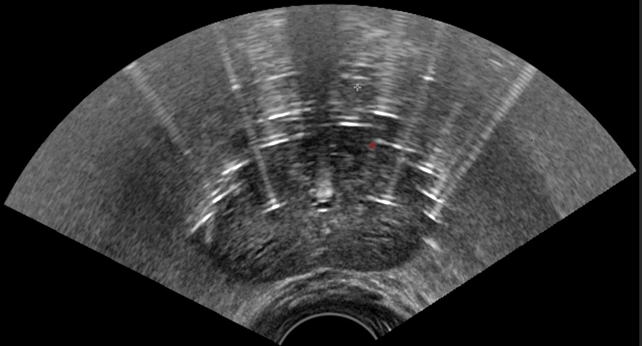

エコーを用いてシードを留置している様子